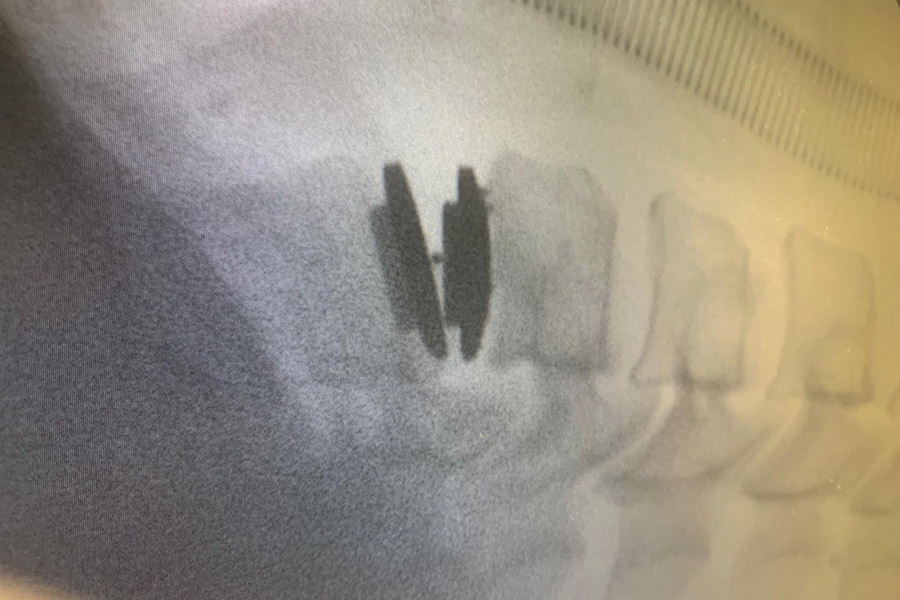

Caso clínico: endoscopia de columna multinivel L4L5 y L5S1

Los síntomas que presentaba el paciente eran dolores acentuados en las piernas, claudicación a la marcha y calambres y hormigueos en las piernas.

Durante la intervención quirúrgica, se abordarán los dos niveles mediante la técnica de endoscopia de columna.